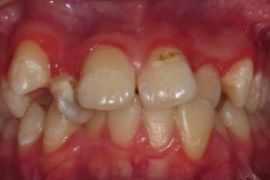

①↑歯肉炎・歯周炎の状態です.

診査にて「歯肉炎または歯周炎」と診断された場合.歯石等の炎症を誘発する物質を取り除きながら,歯周ポケット内の除石,殺菌のために歯科用パルス発振レーザー照射治療を数回行います.

・治療療前(写真左):中等度の歯周炎です.